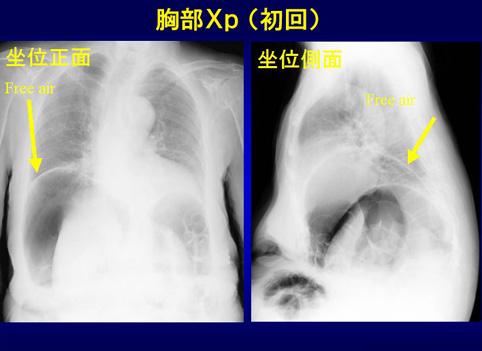

A case of pneumatosis cystoides intestinalis which showed pneumoperitoneum.

[Image-ID:11612]

Lesión que asemeja tumoración/Enfermedad enfisematosa quística intestinal

colon/lesión que abarca dos o más regiones del colon

Rayos X